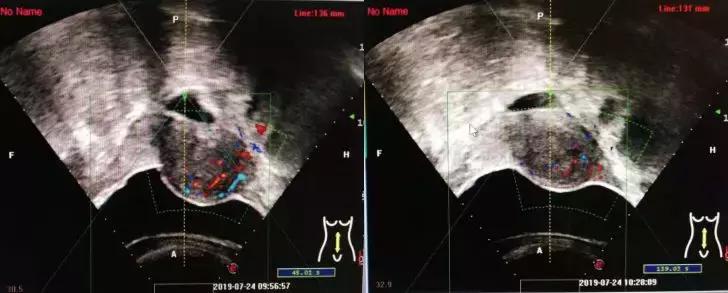

下面四组影像学资料为其中一名子宫肌瘤患者在治疗前、治疗中以及治疗后的影像学表现。

术前超声示血流丰富

消融术中表现

消融术后表现